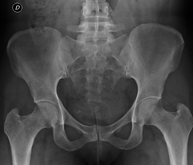

- Pelvis X-ray

This procedure uses X-ray imaging to examine the pelvis, especially the pelvic bones.

- Sacroiliac X-ray

This procedure uses X-rays to examine the sacroiliac joints and rule out inflammatory, traumatic or degenerative diseases.